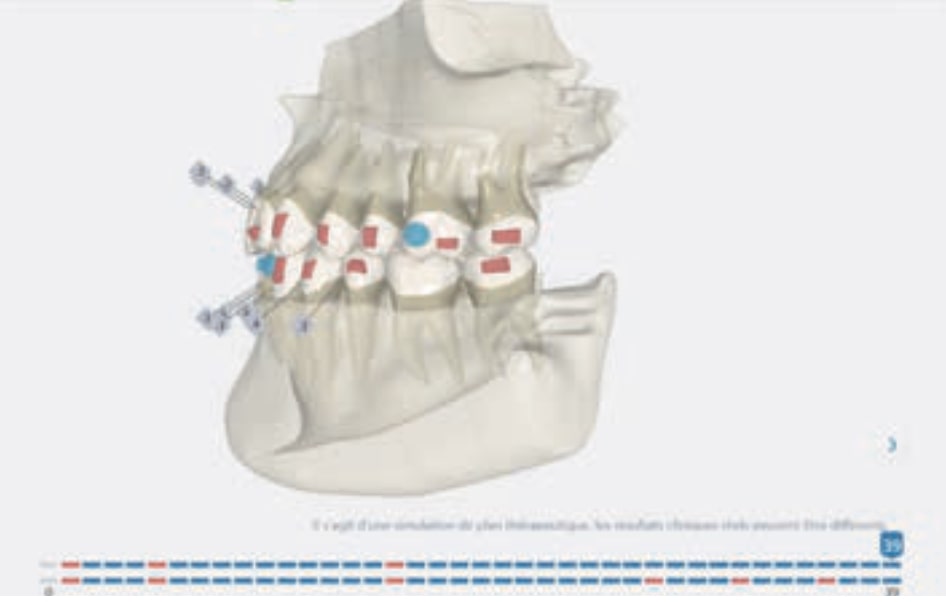

Treatment setup